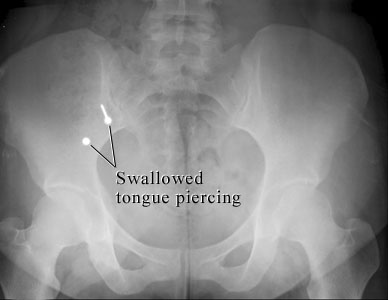

Body Piercing ProblemCourtesy of Intermountain Medical Imaging, Boise,

Idaho. This X-ray of the belly shows two metal parts inside the bowel that were swallowed

from a tongue piercing. The sharp stud could cause problems, while the blunt

part is not likely to cause problems. Both parts are likely to pass in the

stool. ByHealthwise Staff Primary Medical ReviewerWilliam H. Blahd, Jr., MD, FACEP - Emergency Medicine Specialist Medical ReviewerH. Michael O'Connor, MD - Emergency Medicine Martin J. Gabica, MD - Family Medicine Current as ofMarch 20, 2017 Current as of: